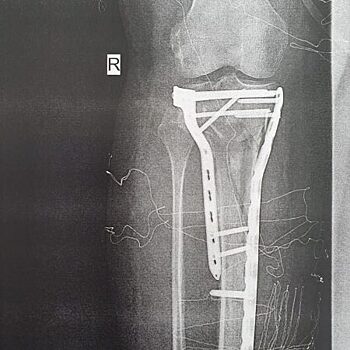

В Красногорскую городскую больницу № 1 поступила пациентка с оскольчатым переломом голени. Травму 61-летняя женщина получила в результате падения с электросамоката. «Это был максимально сложный перелом данного сегмента — оскольчатый, со множеством фрагментов. При поступлении пациентке был наложен аппарат внешней фиксации, а вторым этапом выполнен демонтаж аппарата и остеосинтез пластинами. Операция прошла успешно», – отметил врач травматолог-ортопед Красногорской городской больницы №1 Сергей Косарев. Несмотря на то, что операция прошла успешно, пациентка долго будет восстанавливаться, говорят врачи. Сейчас женщине нужно разрабатывать ногу и наблюдаться у хирургов. Врачи напоминают о влажности соблюдения режима самоизоляции, это позволит сохранить здоровье и предотвратить заболевание коронавирусной инфекцией. А мы, со своей стороны, аплодируем землячке. Чай, «не шашнадцать» ей – и падение с электросамоката! С электросамоката, Карл! Желаем скорейшего выздоровления! Материал предоставила пресс-служба Красногорской городской больницы № 1 © zemlyak.news